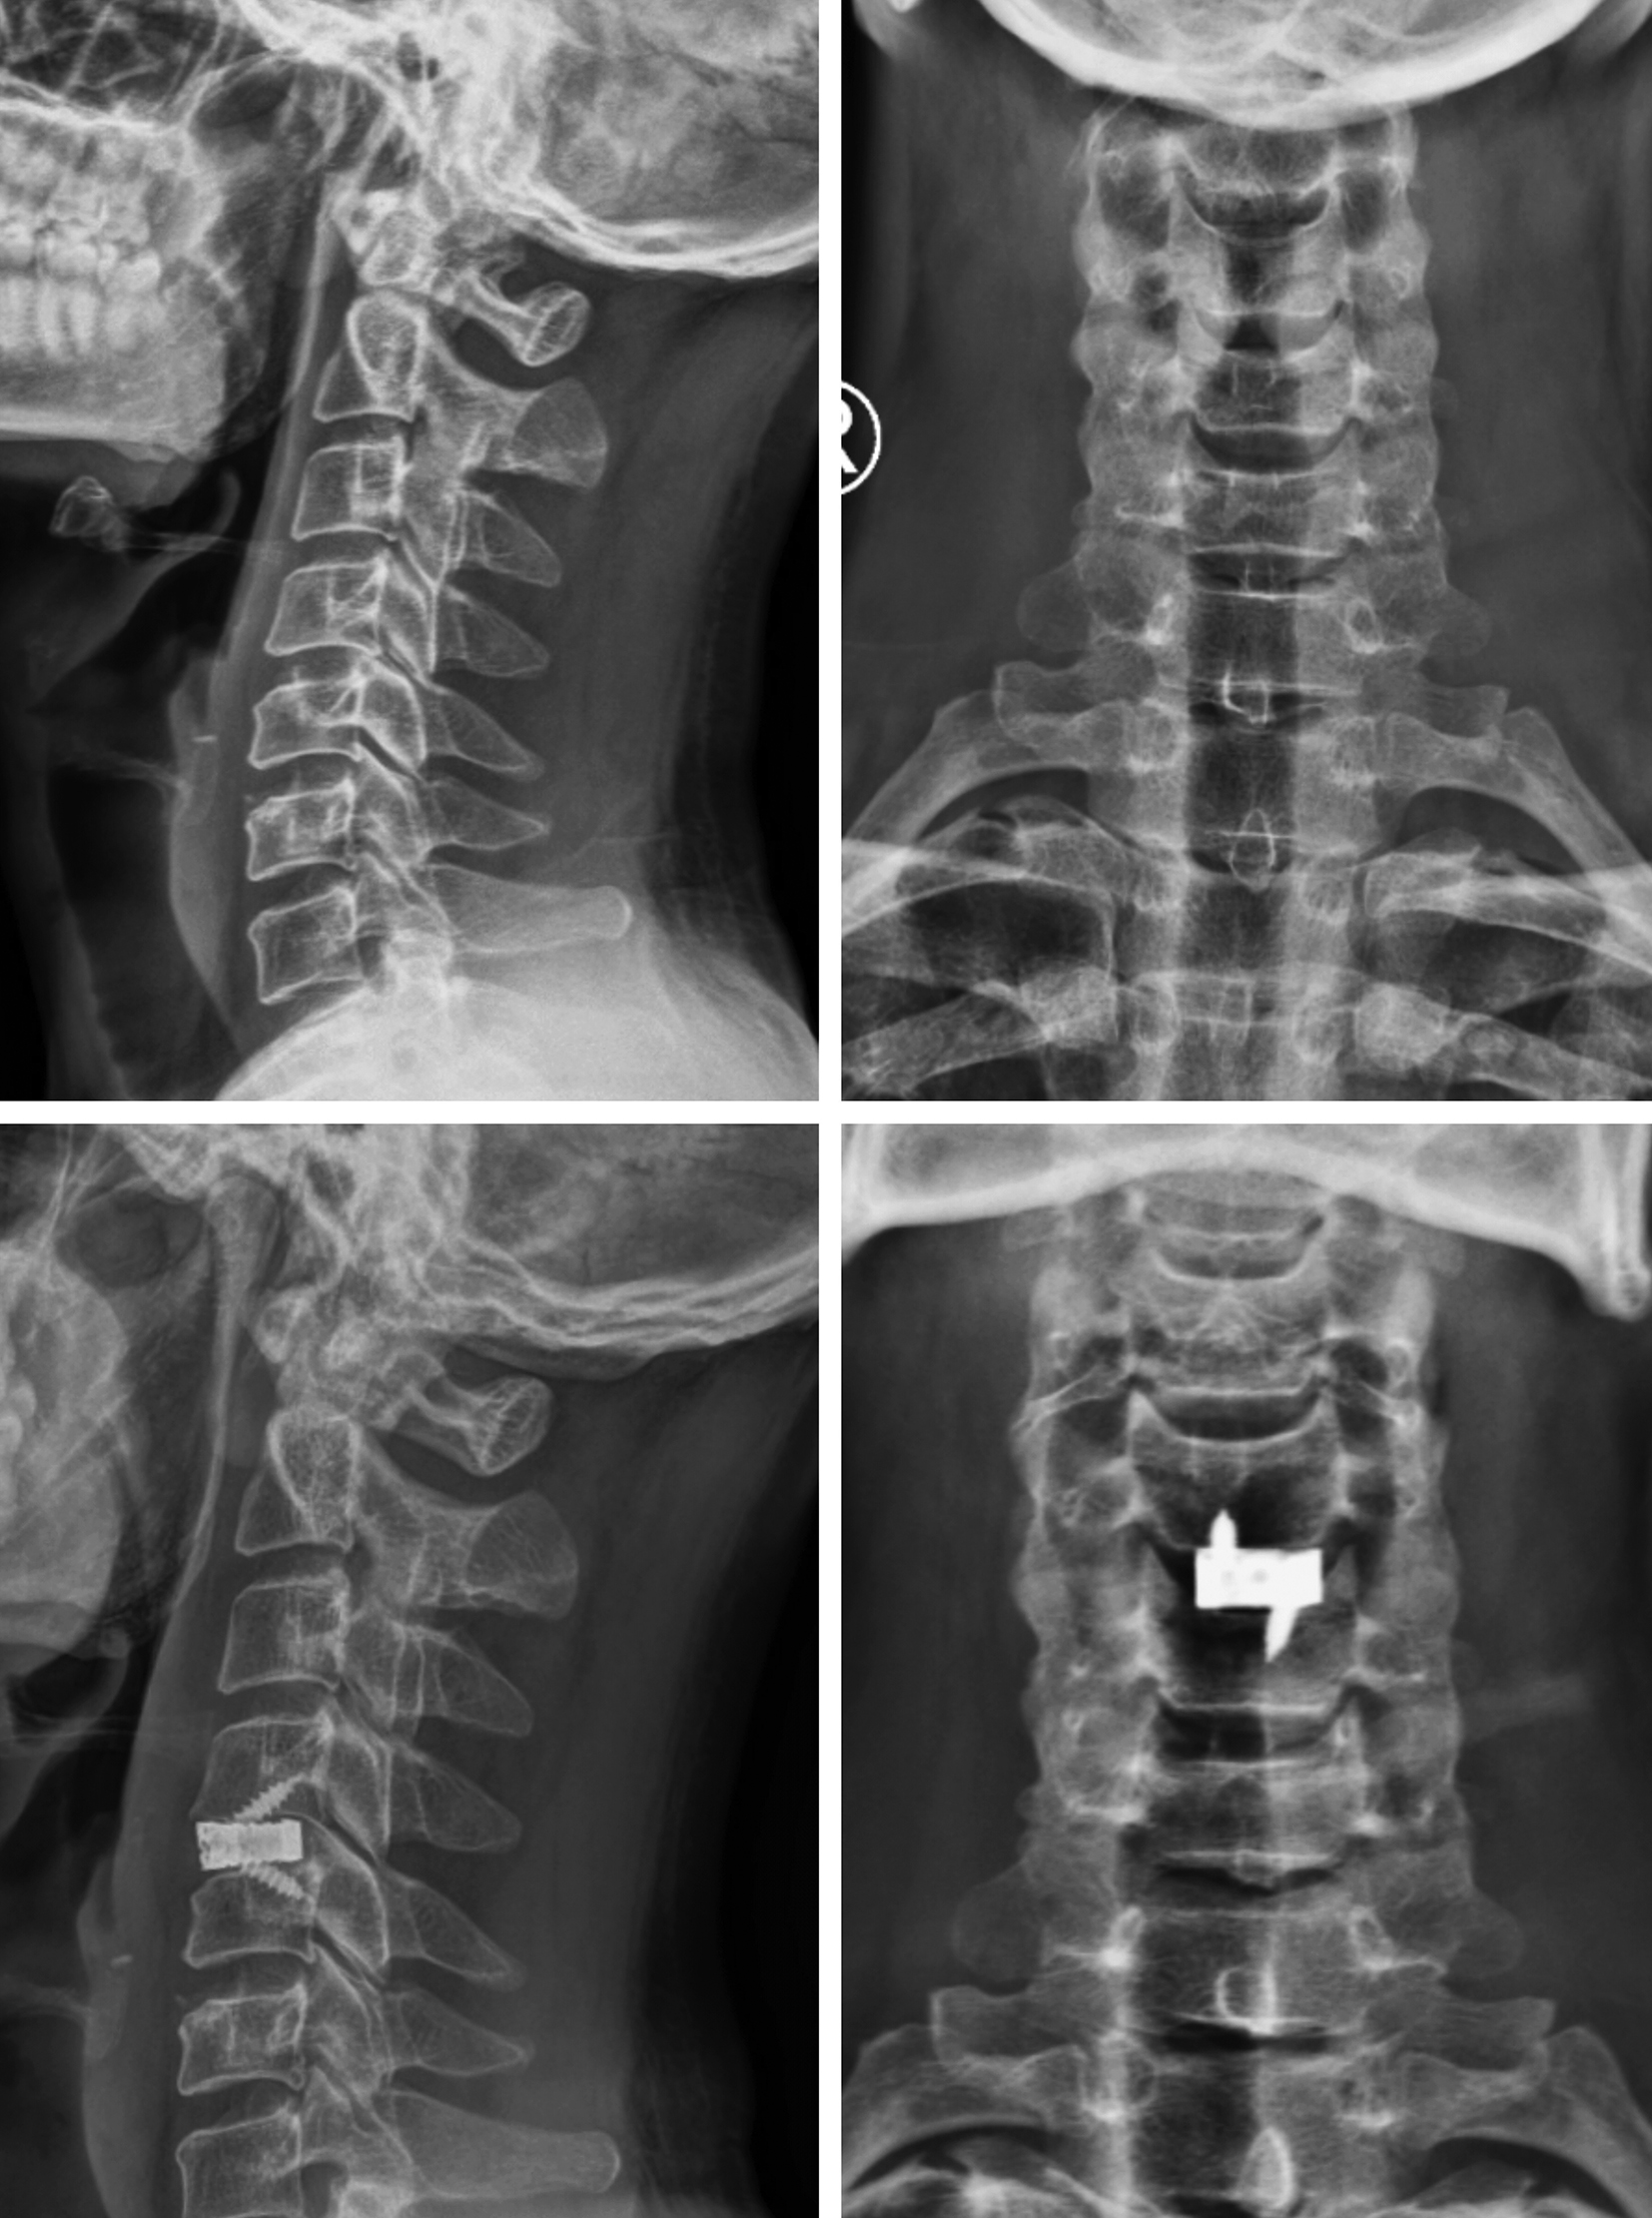

Figures 1-4 show pre-operative and post-operative radiological images in few of our patients.

Figure 4. A - Preoperative radiographic imaging study of the cervical spine (sagittal view) showing disc-osteophyte complex causing narrowing of the central canal; B - Preoperative radiographic imaging study of the cervical spine (coronal view); C - Postoperative radiographic imaging study of the cervical spine (sagittal view) showing the cage with screw in situ; D - Postoperative radiographic imaging study of the cervical spine (coronal view) showing the cage with screw in situ